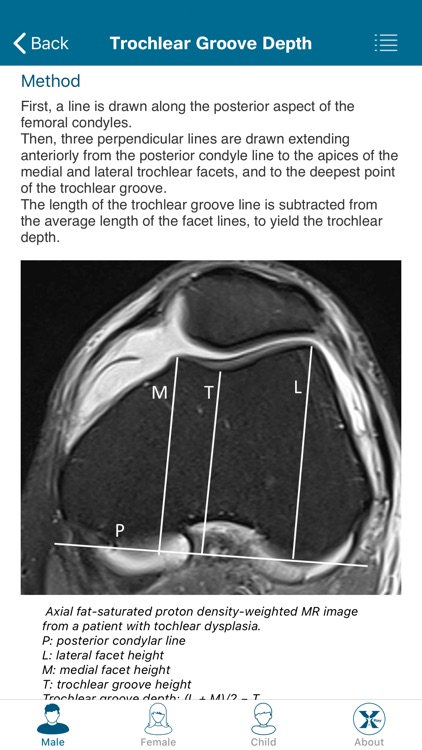

Created by radiologists for all those who practice medical imaging, this application constitutes an atlas of the main measurements in radiology and their normal values based on the most cited literature. It illustrates easy and reproducible methods using different imaging methods.

Created by radiologists for all those who practice medical imaging, this application constitutes an atlas of the main measurements in radiology and their normal values based on the most cited literature. It illustrates easy and reproducible methods using different imaging methods.

The application covers multiple imaging modalities: radiography, ultrasound, CT and MRI. The modules are divided into six sub-specialties: osteoarticular, cervical region, thorax, cardiovascular, abdomen and pelvis.